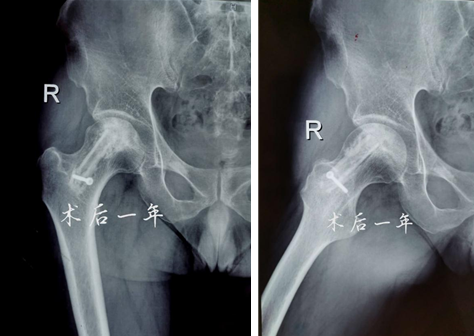

术后一年

术后12个月和24个月,患者来院复查,影像片子显示患者右侧股骨头髋臼平整光滑,股骨头圆润光滑,股骨头内骨小梁密度均匀,已恢复至正常股骨头状态,几乎与正常人股骨头无异。患者随访时说:“来财神捕鱼 之前,我独立行走都困难,短短几米的距离,我可能要花费三四分钟才能走完。手术之后,我不仅可以健步如飞,还能做下蹲等动作,也不必担心重体力劳动导致股骨头无法承受的问题,这个手术真的是太好了,不仅救了我,也救了我一家人……”